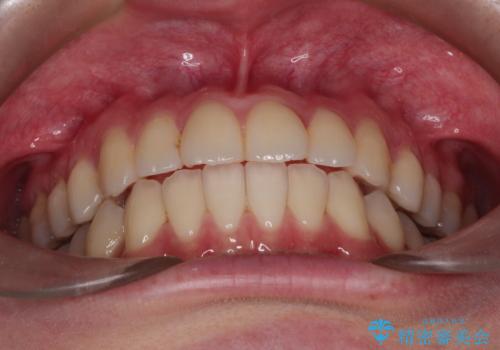

インビザラインによる非抜歯矯正 ガタガタな歯並びを整った歯並びへ

- 前歯のガタガタを主訴に来院されました。

抜歯矯正も考えられる状態でしたが、非抜歯矯正を希望されました。

また人前でお話する機会もあるとのことだったので、目立たない装置をご希望されインビザラインで治療を行うこととなりました。

使用時間を守っていただけたので、スムーズに治療を終わることができました。